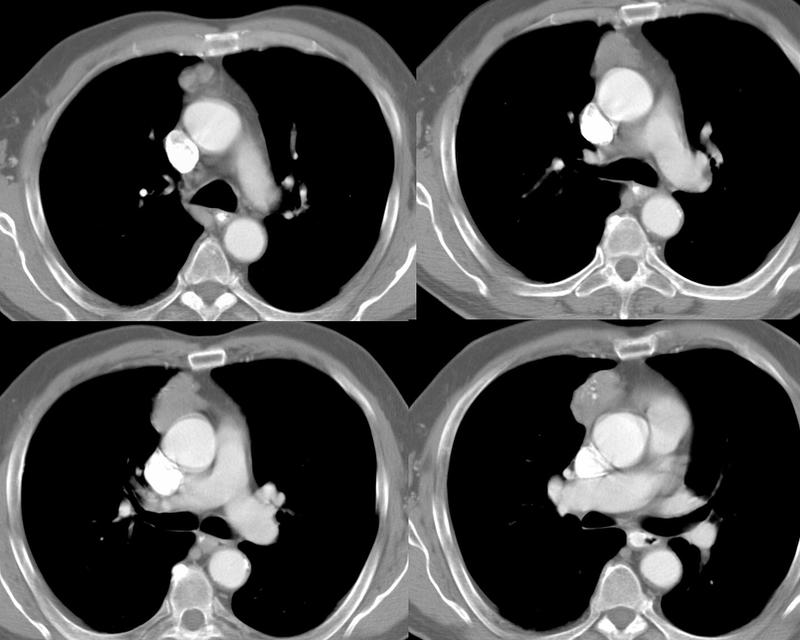

Thymoma